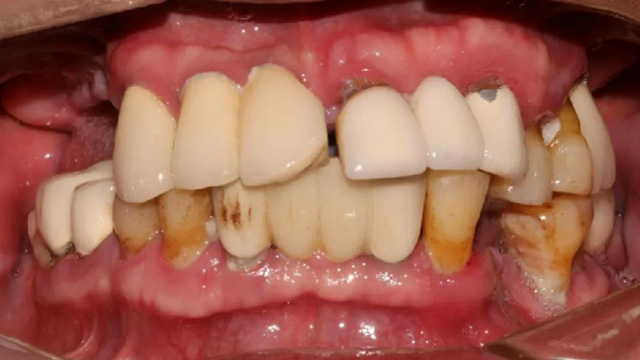

吴叔叔当时的口腔情况

经过检查,余国庆医生发现吴叔叔的口腔情况比较复杂。检查报告显示,他口腔里现存完整的种植牙只有两颗,上下颌各1颗。

“上面种了4颗,断了两颗,脱落1颗,只有1颗能用,下面有一颗牙冠脱落,另一颗有种植体周围炎,有明显的骨吸收。”吴叔叔剩下的天然牙也不好,做了几处修复,之前的牙冠修复用的都是烤瓷牙,有好几颗磨损严重露出了金属。由于存在缺牙、不良修复体等情况,口腔整体咬合紊乱,进食很困难。